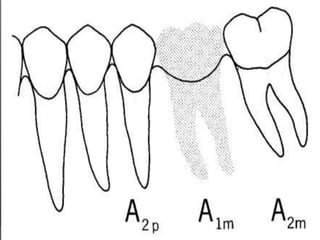

EVALUACIÓN DE PILARESProporción corona-raizConfiguración de la raízZona del Ligamento Periodontal (Ley de Ante)

Tylman: afirmó que dos dientes pilares son capaces de soportar dos póntIcos.Johnston y col.: LEY DE ANTELa superficie radicular de los dientes pilares, con soporte óseo periodontal, debe ser mayor o igual a la de los dientes a sustituir con pónticos